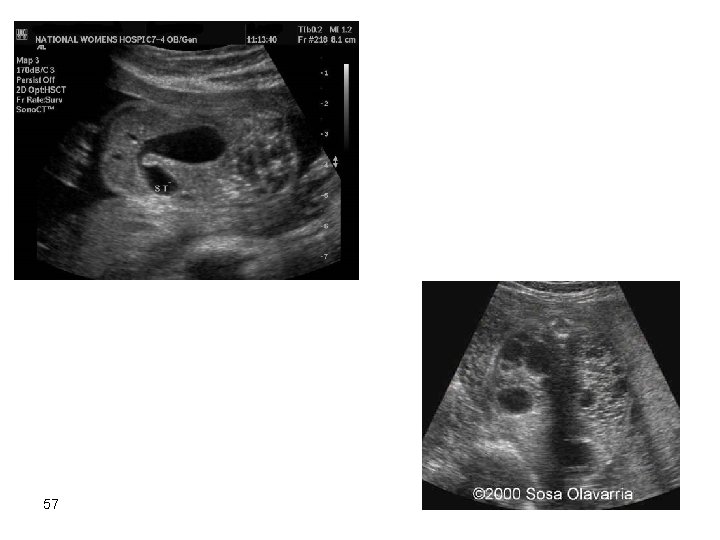

Gastrointestinal Tract Anomalies The prognosis is generally good after surgical correction [provided NO other anomalies co-exist] Malformations presenting with intestinal obstruction: Bowel obstruction above the ileum. All usually results in polyhydramnios due to failure of absorption of swallowed amniotic fluid. After delivery there is vomiting and abdominal distension. Surgery at early neonatal life is successful in duodenal atresia, esophageal atresia, pyloric stenosis, jejeunal and ileal atresia. Bowel obstruction below the ileum. Generalized distention of bowel loops on ultrasound The causes are: – 56 – – – Dysfunctional: the distention may be transient and resolve spontaneously. Meconium ileus. Anal atresia and imperforate anus. Hirschsprung’s disease

57